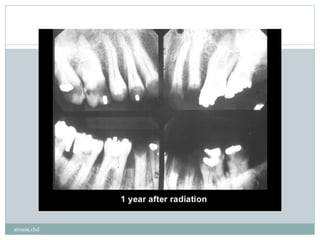

Rampand caries

‫به‬‫با‬ ‫ها‬ ‫بچه‬ ‫در‬ ‫که‬ ‫گویند‬ ‫می‬‫نده‬‫و‬‫پیشر‬ ‫سریعا‬ ‫و‬ ‫شدید‬ ‫پوسیدگی‬‫تخریب‬ ‫به‬‫دهانی‬ ‫داشت‬

‫شود‬ ‫می‬‫دیده‬ ‫غذایی‬‫بد‬‫وعادات‬ ‫ضعیف‬.

‫شدید‬ ‫پوسیدگی‬ ‫ت‬‫ر‬‫صو‬ ‫به‬ ‫افی‬‫ر‬‫گ‬ ‫ادیو‬‫ر‬‫در‬ ‫که‬(‫پیشرفته‬)‫دندان‬ ‫در‬ ‫خصوص‬ ‫به‬‫قدامی‬ ‫های‬

‫شود‬ ‫می‬‫دیده‬ ‫پایین‬ ‫فک‬.